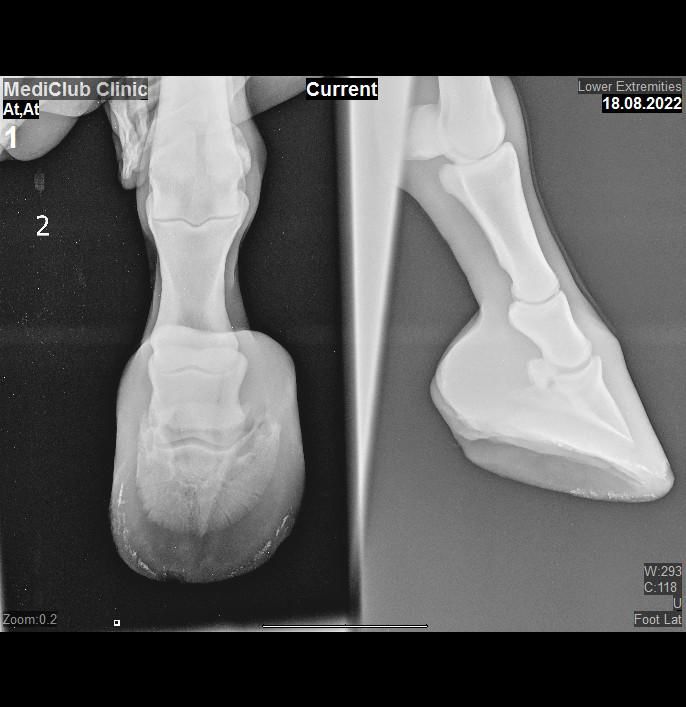

Мы нашли нового врача, который сразу по походке сказал, что хромота из-за трещины в серединной бороздке.На всякий случай сделали рентгены(на человеческом рентгене, другого у нас нет), сказал никаких проблем, деформаций, переломов и т.д.Нужно лечить стрелку(мазь в трещину и антибиотики колоть).Я выкладываю рентгены переднего правого, сняли как смогли, надеюсь хоть как-то информативно.На прошлой неделе в четверг его расчистили, выставляю свежее фото также.Первые два переднего правого, последние два переднее левое.Поделитесь своим мнением пожалуйста??